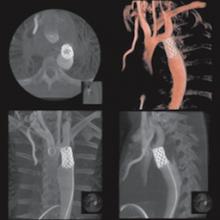

As catheter-based, minimally invasive procedures expand rapidly beyond treatment of the coronary arteries into all areas of the human anatomy, angiography X-ray imaging systems have moved beyond their original purpose of simple vascular imaging. Today, in addition to interventional cardiology, cath labs are frequently shared by numerous specialists, including interventional radiology, interventional oncology, electrophysiology (EP), vascular surgeons and neurology.